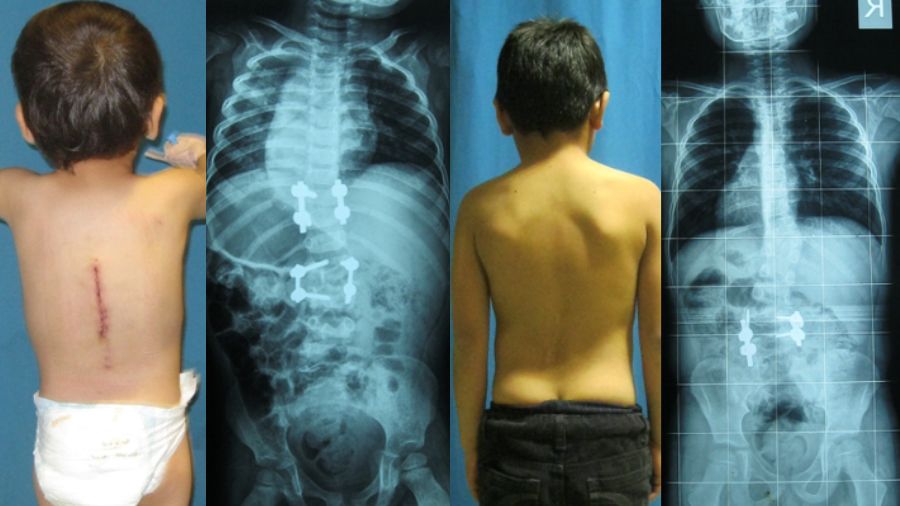

At AasthaLok Hospital, Dr. Mahesh Prasad specializes in Lateral Mass Screw Fixation, a highly effective technique for treating cervical spine instability and injuries. This surgery helps stabilize the spine, reduce pain, and improve nerve function — enabling patients to return to their normal lives faster 💪.